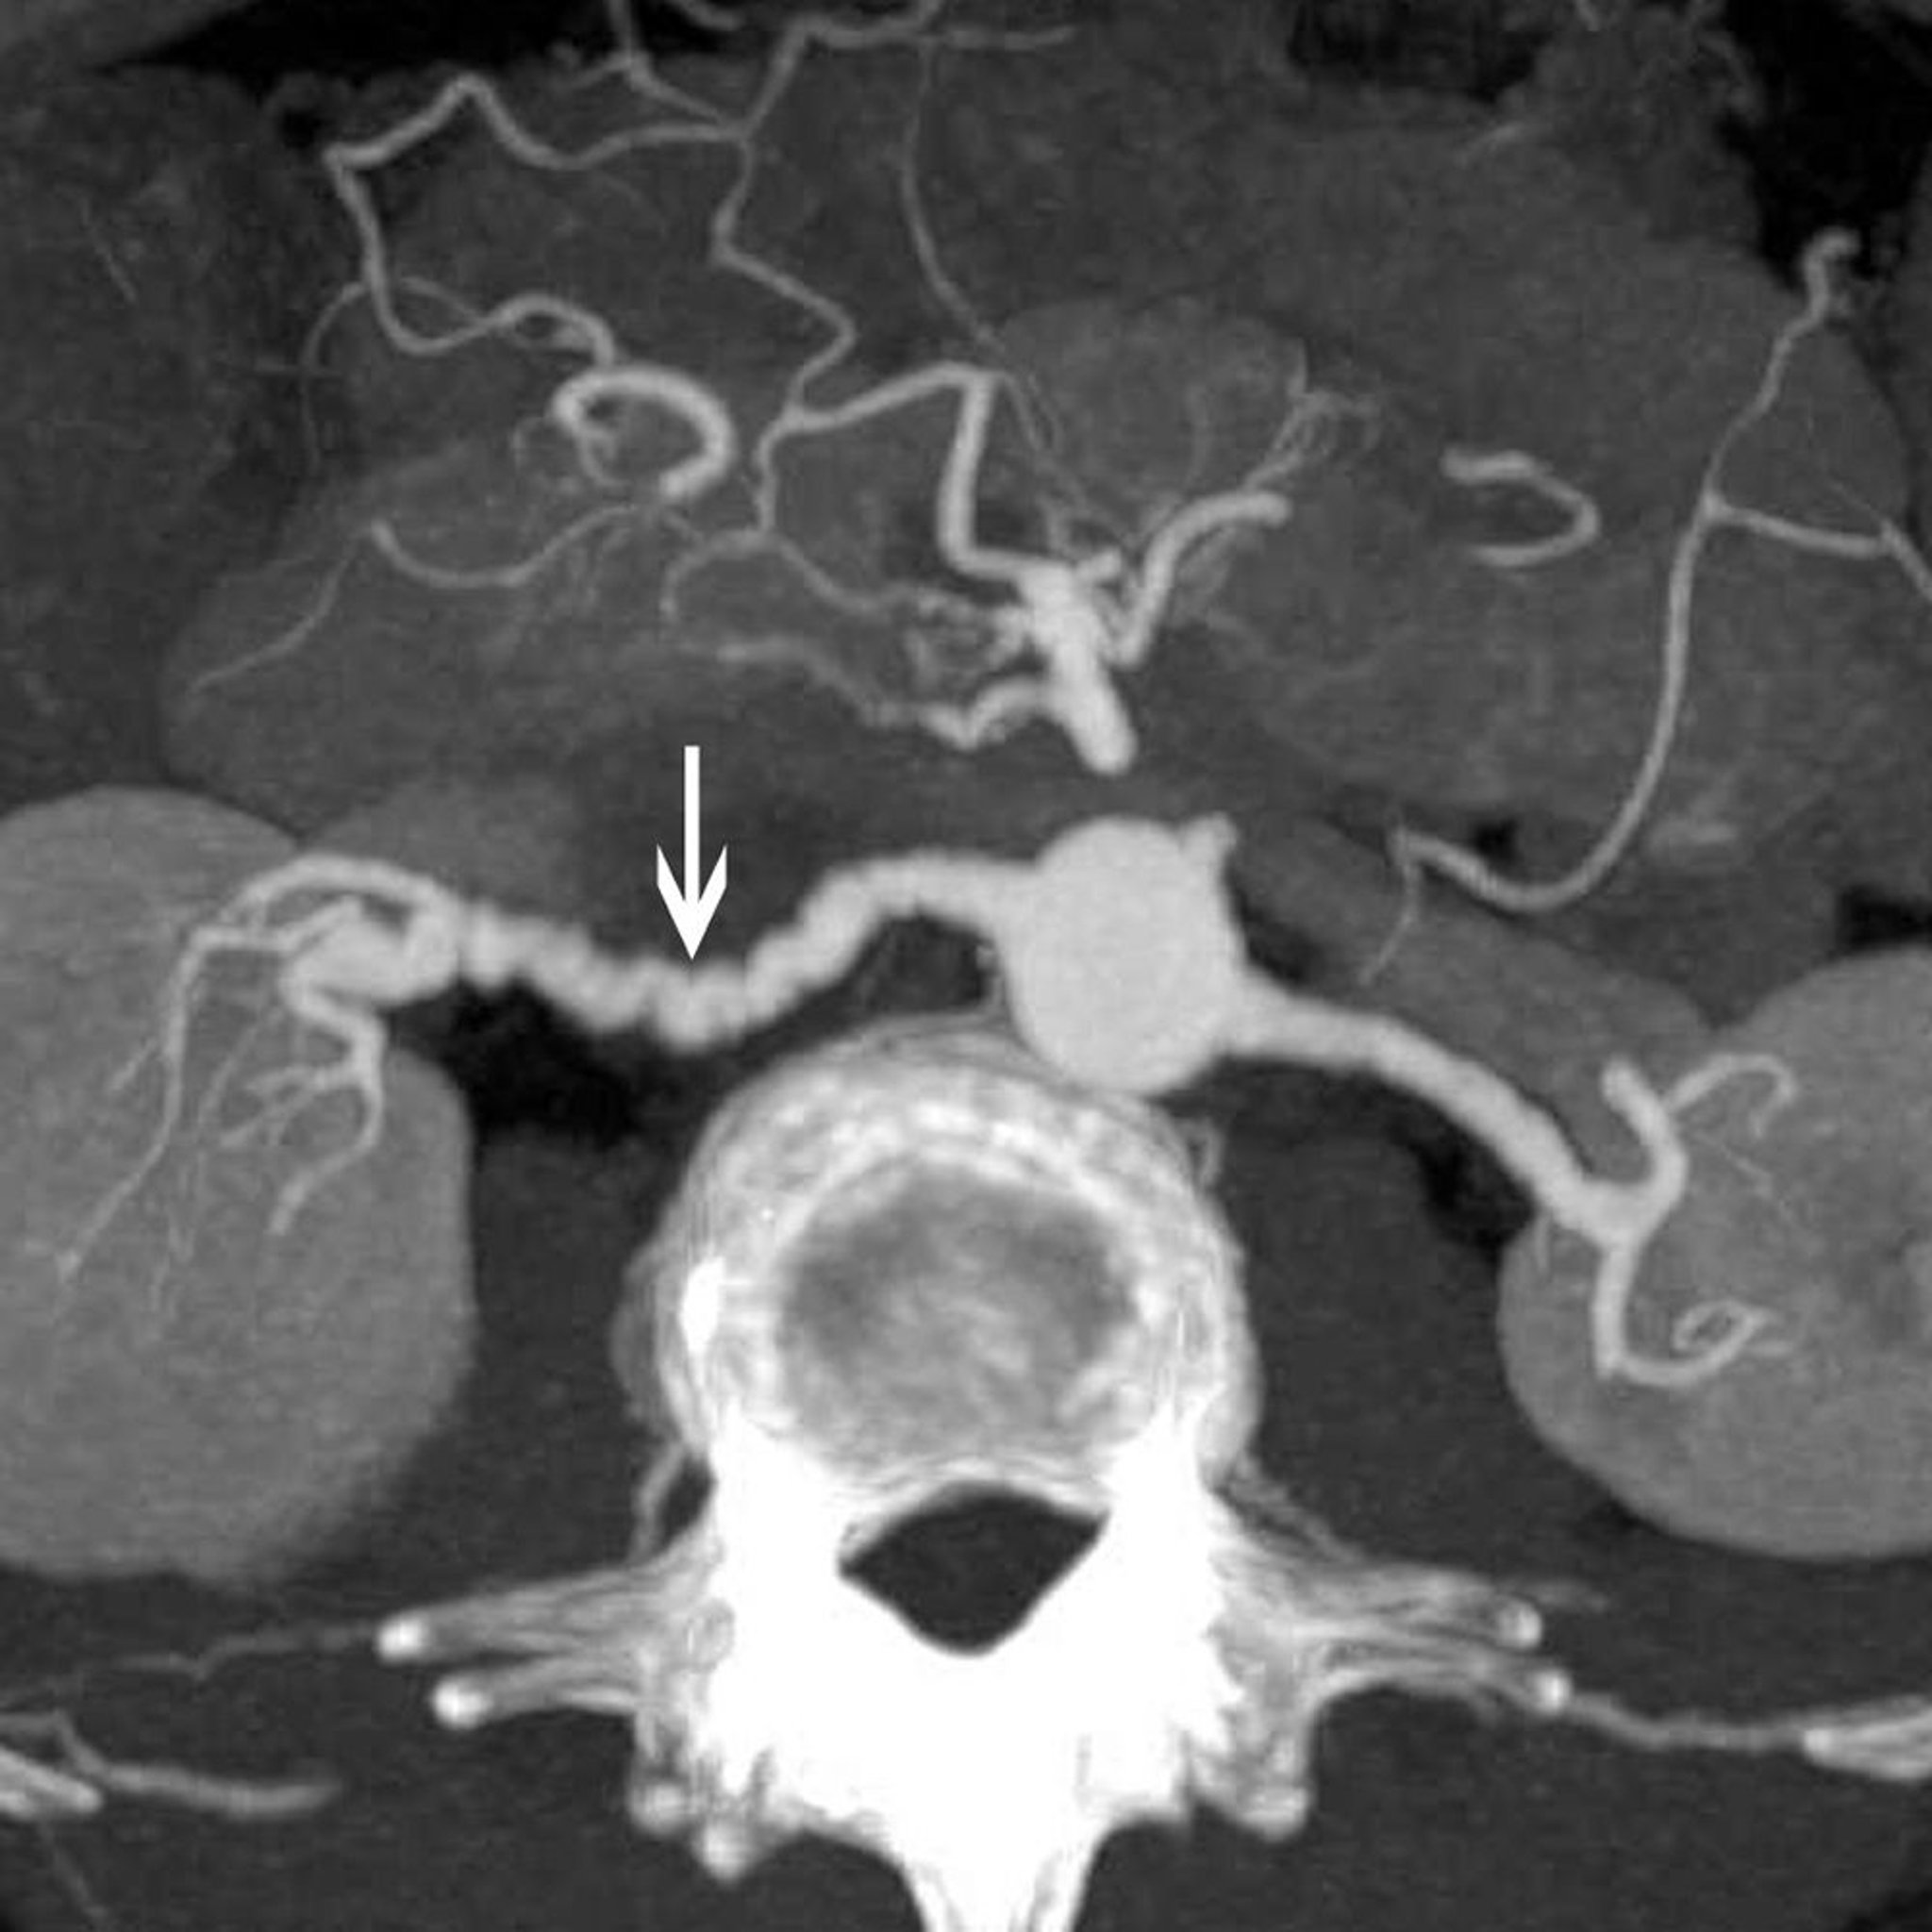

腎動脈の線維筋性異形成

この画像には,腎動脈に線維筋性異形成がある患者の古典的な「念珠状(string of beads)」所見(矢印)が認められる。

© 2017 Elliot K.Fishman, MD.